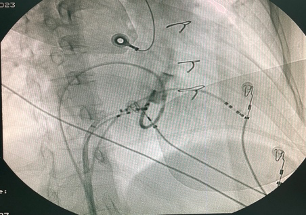

Tiến hành map vùng sau vách bên phải vòng van 3 lá ghi nhận điện thế nhĩ thất hoà vào nhau tương tự sau vách bên trái. Tiến hành cắt đốt vị trí này thì chấm dứt đường phụ nhưng sau đó tái phát lại. Tiến hành thăm dò vùng vị trí thượng mạc trong lỗ tĩnh mạch vành hướng về bên trái ghi nhận điện thế nhĩ thất hoà vào nhau làm 1, tiến hành cắt đốt vị trí này thì chấm dứt hoàn toàn đường dẫn truyền phụ này. Bệnh nhân khôi phục nhịp xoang dẫn truyền hoàn toàn qua nút nhĩ thất thông thường.

Hình: vị trí cắt đốt thành công trong xoang vành bằng catheter năng lượng cao và hình ảnh xoang vành.